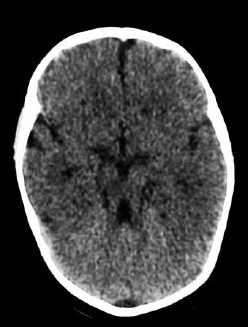

Paciente com atraso global do desenvolvimento, ataxia e apraxia oculomotora apresenta o achado de imagem a seguir.

O diagnóstico é